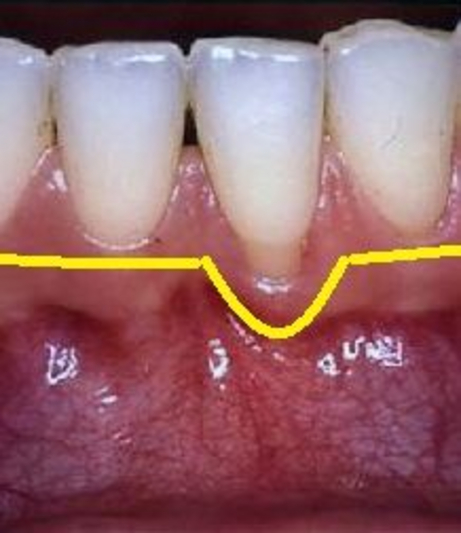

L’approccio chirurgico chirurgia osseo resettiva consiste nel rimuovere il tessuto malato (la tasca) e nel ricontornare i tessuti molli (gengive) e duri (osso alveolare) rendendone uniforme l'alteza e rimuovendo picchi e irregolarità. Eliminando le anomalie del tessuto osseo e gengivale che determinano un'accumulo di placca è possibile infatti ottenere un’anatomia che permetta l’eliminazione permanente delle tasche, dei difetti ossei e di favorire le manovre di igiene domiciliare.